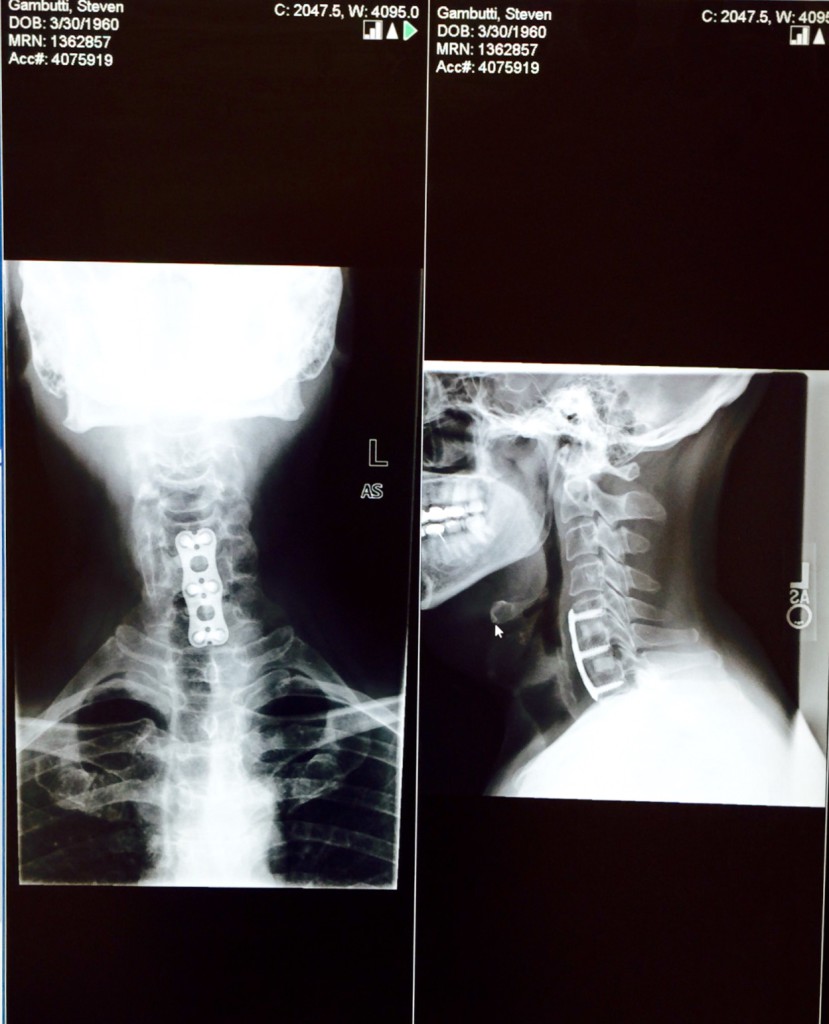

I started experiencing shoulder and arm pain in February of 2015. It took several months before I was properly diagnosed with herniated discs in my cervical spine. Meanwhile my symptoms progressed through the spring and early summer to the point where it was painful to perform routine tasks like driving and working at the computer. Most upsetting, my workout regimen of weightlifting and cardio had become impossible to maintain. I was devastated at the idea of needing spinal fusion. With my diagnosis in hand, I immediately contacted HSS for an appointment aware of their reputation for excellence. Dr. Bernard Rawlins immediately confirmed my diagnosis and we scheduled surgery for August. I had read Dr. Rawlins' bio on the HSS web site and after our first meeting I had complete faith in his ability. The thoroughness of all the staff at HSS furthered my confidence. I am happy to say the road was hard, but not long due the the expertise of my surgeon. In only six months I am back to where I was before the injury. I don't believe I would have achieved the same results if i had gone anywhere else. Amazing.